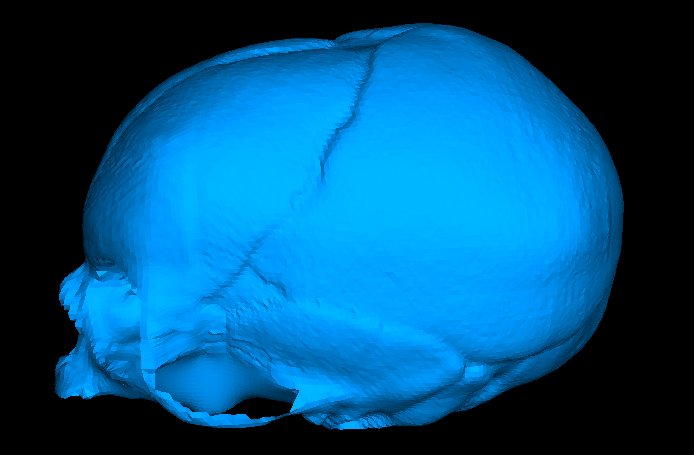

Snapshots of the change of shape of the fetal skull from applying obstetric forceps are shown below (left is undeformed; right is deformed). Note that deformations are magnified with a factor 4.